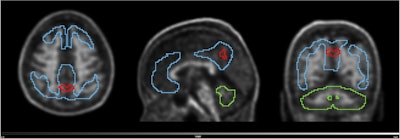

Volume with higher baseline signal for N1 accumulators and N1 non-accumulators of amyloid (red line) overlayed on the scan of an N1 accumulator (MNI space). Grey scale shows SUVR range. Blue line shows the Centiloid target region and the green line shows the reference region (whole cerebellum).European Journal of Nuclear Medicine and Molecular Imaging

To identify the region highlighted in red, an amyloid-negative population (at baseline) with subjective cognitive decline was assessed with a voxel-based analysis using standardized uptake value ratios (SUVRs). Then, the baseline SUVR images of amyloid accumulators versus nonaccumulators were compared. Amyloid accumulation status was defined using the Centiloid method and with a five-year follow-up, Kolinger said.

The results showed that accumulators exhibited higher baseline SUVR in the red-marked region, which corresponds to part of the precuneus, a brain area known to play a role in early Alzheimer's disease. This region overlaps with the Centiloid target region (shown in blue), underscoring the potential of this approach to enhance preclinical Alzheimer's disease assessment, Kolinger added.